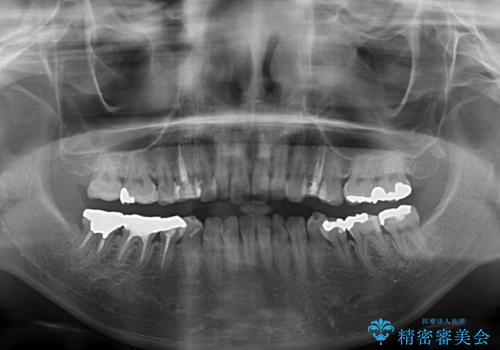

総合歯科治療 矯正治療と失活歯のセラミック補綴治療

- 失活により変色した歯と不揃いな口元を気にして来院された患者様です。

口元をインビザラインにより歯列を整え、その後に失活している奥歯をオールセラミッククラウンにて補綴治療することとしました。